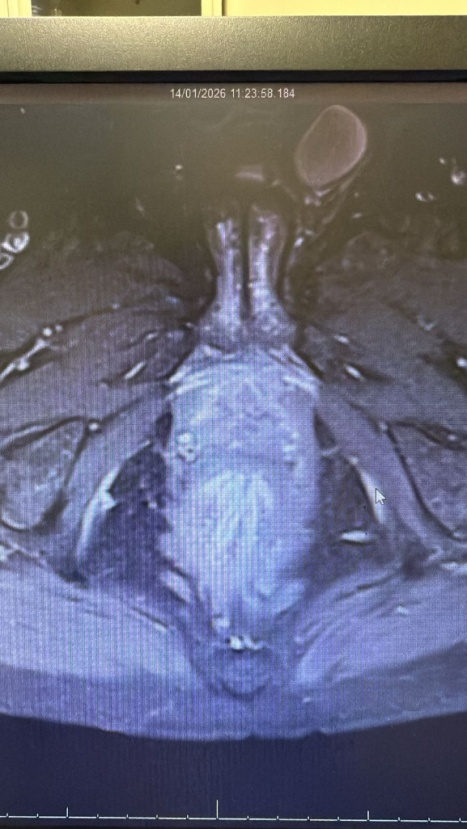

• 3) Imaging: Ultrasound revealed a thickened, edematous scrotal sac with a loculated collection (35 × 10 mm) at the posterolateral aspect, suggestive of cellulitis and abscess formation [3]. MRI confirmed an irregular fluid collection within the corpus spongiosum at the level of the superior pubic ramus, extending to the prostatic urethra with intense enhancement of the soft tissues [4]. Figures 1-3 show the pre operative MRI.

Figure 3. Axial post-contrast T1-weighted MRI demonstrating peripheral rim enhancement of the periurethral collection, confirming abscess cavity formation with surrounding inflammatory changes.